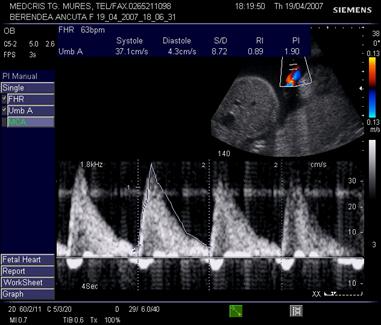

Aspecte patologice anormale ale examenului Doppler ombilical

Daca rezistenta placentara creste, viteza reziduala in diastola se reduce, iar IR si IP cresc.

Aspectul IR este patologic peste percentila 90 din curba de referinta, daca frecventa cardiaca fetala este normala. De asemenea, daca doua examinari la 4 sapt. interval indica o stagnare a IR sau o scadere a fluxului diastolic, situatia este patologica.

In situatii de rezistenta placentara si mai crescuta, se poate ajunge la flux diastolic absent, sau componenta diastolica negativa (reverse flow) ceea ce indica o alterare grava a hemodinamicii fetoplacentare. [3,14,17]

Fig. nr. 322. Reverse flow la o sarcina cu insuficienta cardiaca si hidrotorax, 28 sapt.